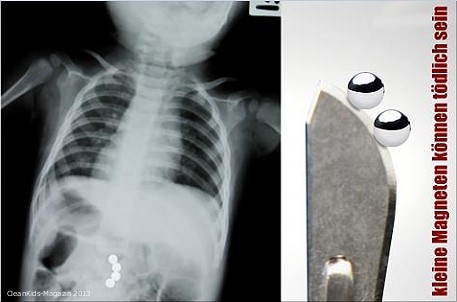

Das Spiel mit diesem Magnetspielzeug kann schlimmstenfalls tödlich enden, wenn Kinder zwei oder mehr der kleinen Magnetteile verschlucken

Das Spielzeug Magnastitix Magnet und Ball Set 60 PCS besteht aus 36 stabförmigen Magneten (rund 2.5 cm lang) und 25 Stahlkugeln. Es besteht die Gefahr von inneren Verletzungen wenn die kleinen Magneten von Kindern verschluckt werden; zudem ist der magnetische Flussindex zu hoch: Das bedeutet, dass sich verschluckte Magnetteile im Darmbereich anziehen könnten und im Darm zu Verletzungen und schlimmstenfalls zu einem Darmverschluss führen können. Anders als bei nicht magnetischen Materialien verlassen die verschluckten Magnetkugeln den Körper nicht mehr auf natürlichem Weg, sondern können sich im Darmtrakt gegenseitig anziehen. Sie klemmen dabei das empfindliche Gewebe ein und können so zu schwerwiegenden inneren Verletzungen führen.

| Produktrisiko: | Die Magneten haben einen hohen magnetischen Fluss, wenn zwei oder mehr verschluckt werden, könnten sie einander anziehen, was eine Darmperforation oder einen Darmverschluss verursacht |